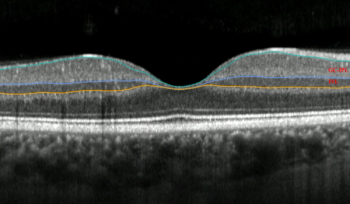

A retrospective observational study shows BCVA was maintained after 6 months for patients with neovascular AMD

Peter K. Kaiser, MD, provides an overview of innovative therapies in development for patients with dry age-related macular degeneration.